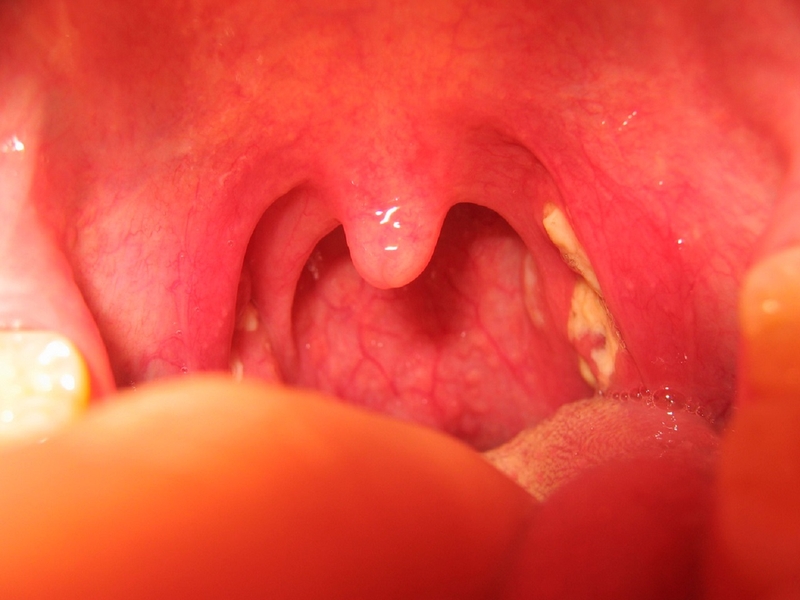

Điều này xảy ra khi amidan bị nhiễm trùng. viêm amidan thường phát triển cùng một số triệu chứng như đau rát cổ họng. Viêm amidan có thể được điều trị bằng thuốc kháng sinh.

Tình trạng này có liên quan đến viêm amidan. Nếu tình trạng viêm amidan không được điều trị dứt điểm sẽ gây mủ tích tụ quanh amidan và những cơn đau dữ dội. Cơn đau thường tồi tệ hơn ở một bên họng, nó có thể lan đến tai và gây đau khi nuốt hoặc ăn uống.